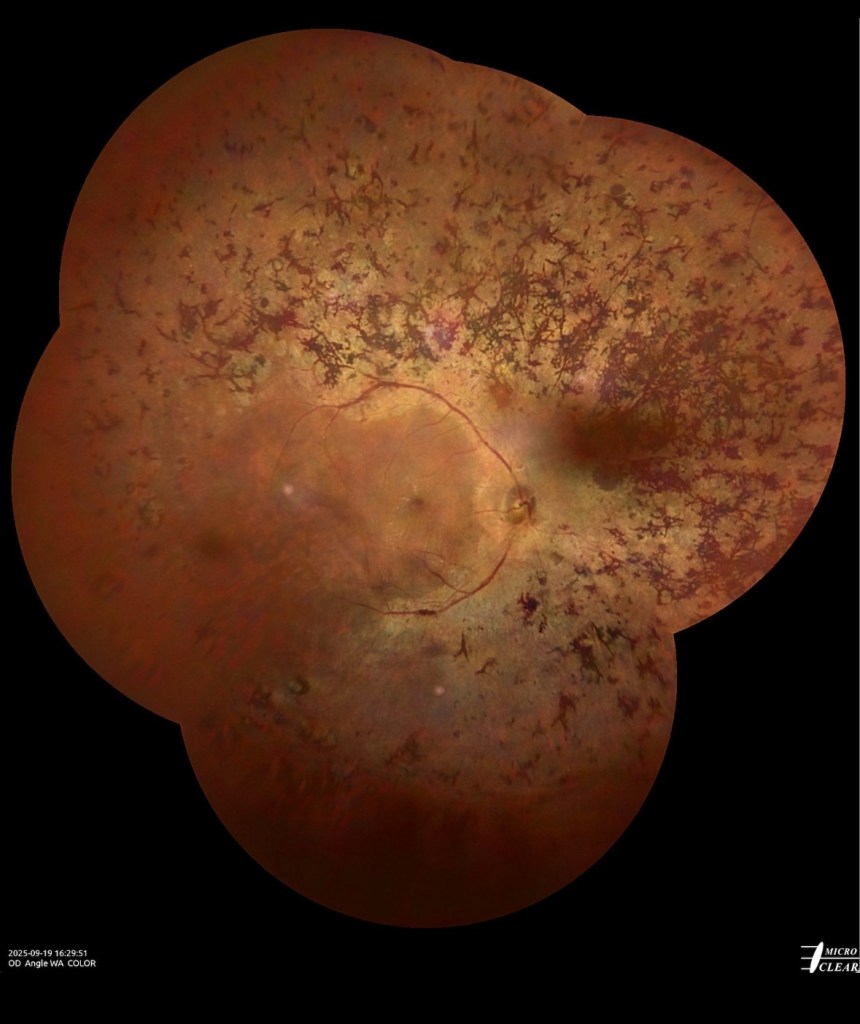

Je souhaite vous partager un cas très intéressant de chirurgie chez un patient atteint de rétinopathie diabétique sévère. Un homme de 63 ans, diabétique, présentait une cataracte modérée et une baisse progressive de la vision, réduite à la perception des doigts. Malgré un traitement clinique antérieur, la maladie avait continué de progresser. Il avait été soumis à des examens du fond d’œil, à une angiographie à la fluorescéine et à une tomographie par cohérence optique.

La procédure a débuté par l’extraction de la cataracte, suivie d’une vitrectomie standard par pars plana, réalisée à travers trois orifices avec un calibre de 23. Une prolifération fibrovasculaire dense a été observée au niveau de la zone maculaire. Une pince crantée de calibre 25 a été utilisée pour engager et soulever le tissu fibreux, qui a été pelé en bloc. Deux échanges air-fluide ont été effectués au cours de l’intervention.